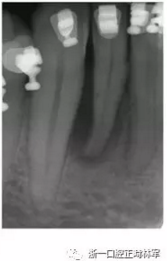

患者42-43區(qū)有復(fù)發(fā)性膿腫,42為兩壁骨袋,遠(yuǎn)中牙周探診9mm(圖12),43探診提示有附著喪失但較穩(wěn)定。患者要求治療膿腫并排齊下頜牙列,因此決定通過(guò)拔除42解決擁擠。方案不采用GTR保留牙齒,通過(guò)正畸拔除42改造骨缺損形態(tài),獲得軟硬組織,避免拔牙區(qū)由于組織的萎縮出現(xiàn)不美觀的裂口。通過(guò)鄰牙的擠壓重建生理性鄰間解剖結(jié)構(gòu)?;颊呤褂蒙鄠?cè)粘接,初期通過(guò)牽引42,43以排齊并修復(fù)43近中骨缺損。隨后緩慢牽引42,42處加轉(zhuǎn)矩扭轉(zhuǎn)牙以增加頰側(cè)骨量并減少軟組織塌陷,避免后期拔牙由于骨皮質(zhì)薄導(dǎo)致的裂縫,先用0.016TMA后用0.017×0.017帶鉤TMA完成(圖13-16)。